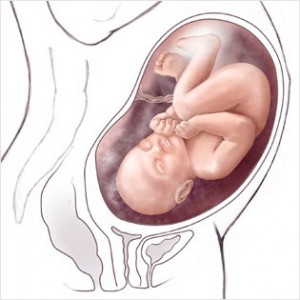

Bu haftadan itibaren artık bebek rahim içerisinde oldukça fazla yer kaplar ve bu yüzden ona hareket edecek fazla alan kalmaz. Eğer bebeğinizin hareketlerinde azalma his ederseniz endişe etmeyin, hareketlerin azalması bu yüzdendir.

Bebeğin Boyutu: 43.7 cm, 1.9 kg